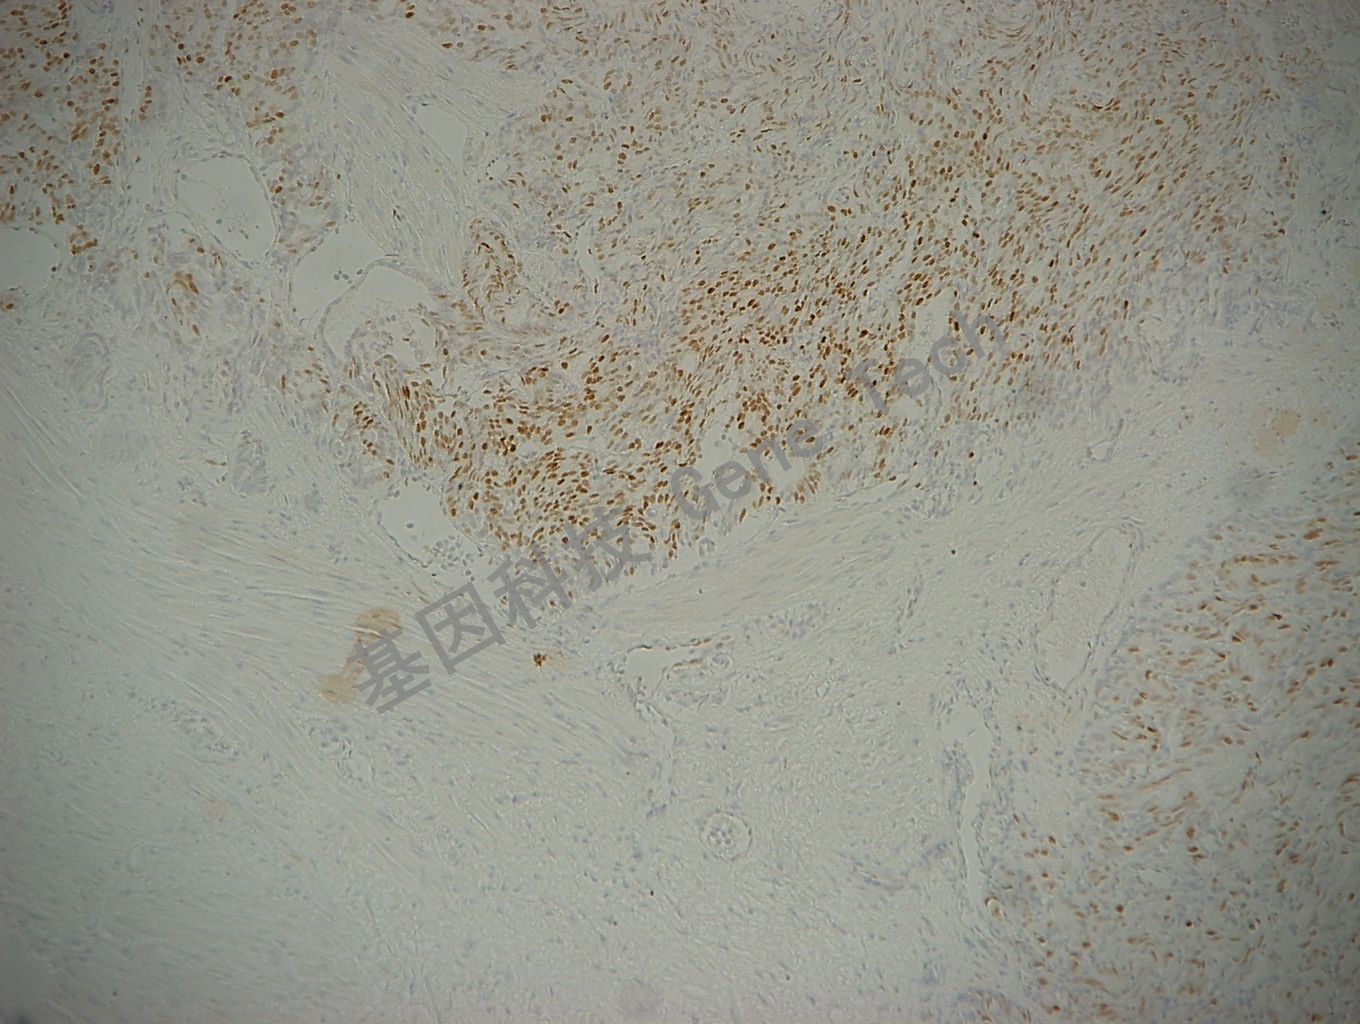

弥漫性大B细胞淋巴瘤石蜡切片,用 c-Myc(GT2206)染色,细胞核阳性,DAB 显色。(10×)